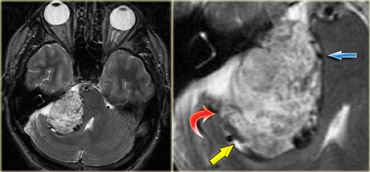

Schwannoma in CPA-region with typical features of an extraaxial tumor (T2WI) Schwannoma in CPA-region with typical features of an extraaxial tumor (T2WI)

The T2W-images show a schwannoma located in the cerebellopontine angle (CPA).

This case nicely demonstrates the typical signs of an extra-axial tumor.

There is a CSF cleft (yellow arrow).

The subarachnoid vessels that run on the surface of the brain are displaced by the lesion (blue arrow).

There is gray matter between the lesion and the white matter (curved red arrow).

The subarachnoid space is widened because growth of an extra-axial lesion tends to push away the brain.

All these signs indicate that this is a typical extra-axial tumor.

In the region of the CPA 90% of the extra-axial tumors are schwannomas.